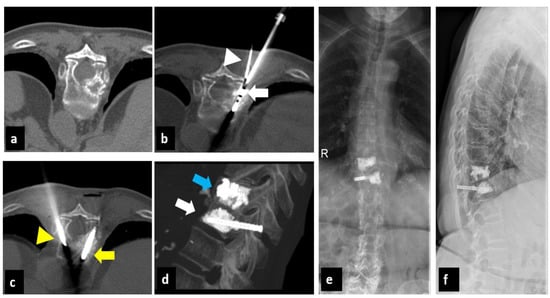

2.1. Treatment Technique